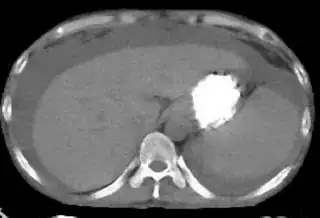

Below I apply two successive morphological openings to the image using a 3x3 circular kernel, and then apply k-means clustering to the gray levels. From your sample images and some I found on the internet, I decided to set k = 4. If you are using high-resolution images, first downsample them to dimensions ~400-600. Otherwise the morphological operation may not have a significant effect, and the k-means will be slow.

Below are some of the opened and segmented images. Of course there's more to be done in terms of

- separating out the liver region

- generalizing this to a large dataset

but hope this is at least a starting point.